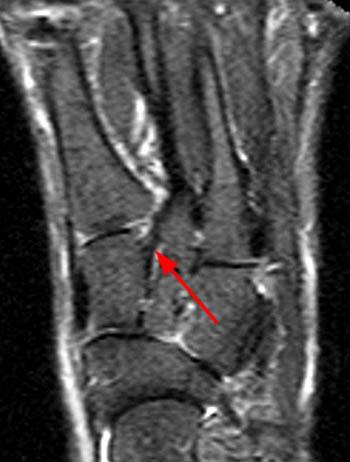

Many sprains happen suddenly, either from a fall, awkward movement, or blow. High Ankle Sprains - Radsource

High Ankle Sprains - Radsource from radsource.us

A fold of peritoneum or other membranes.; It is also known as articular ligament, articular larua, fibrous ligament, or true ligament.other ligaments in the body include the: Aug 13, 2020 · a ligament is a fibrous connective tissue that attaches bone to bone, and usually serves to hold structures together and keep them stable. Cordlike remnants of fetal tubular structures that are nonfunctional after birth. It involves the distal tibiofibular … The ligament complex on the inside part of the ankle is called the deltoid ligament. Ligament, tough fibrous band of connective tissue that serves to support the internal organs and hold bones together in proper articulation at the joints. Many sprains happen suddenly, either from a fall, awkward movement, or blow. The medial deltoid ligament is injured less often. Ligament injuries are common, especially in the: A high ankle sprain is less common in everyday life but can be seen in competitive athletes. noun a tough fibrous band of tissue connecting the articular extremities of bones or supporting an organ in place. Review date 8/13/2020 updated by: